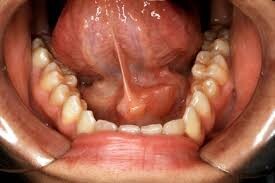

Firstly, what is the submandibular gland? There is one walnut-sized submandibular gland on each side of the face, just in front of the curve of the lower jaw at the back of the mouth. Along with your other salivary glands, these glands supply saliva that contains enzymes to help break down food and minerals that reduce the damaging effects of food acids on your tooth enamel. Saliva also makes the food you chew wet and easy to swallow.

If you feel swelling underneath your lower jaw, it could be a swollen submandibular gland. Swollen submandibular glands are usually caused by tiny stones blocking the ducts that channel saliva into the mouth. According to the Merck Manual, these stones can develop from the salts in saliva, especially if a person is dehydrated. When a stone blocks a salivary gland, a condition known as sialolithiasis, an individual may experience swelling and pain over the affected gland. Why these stones form isn't clearly known, though they can be associated with liver disease and gout. According to The Journal of Medical Research, sialolithiasis is the most common salivary gland disease, and the submandibular gland is affected in 83 percent of cases.